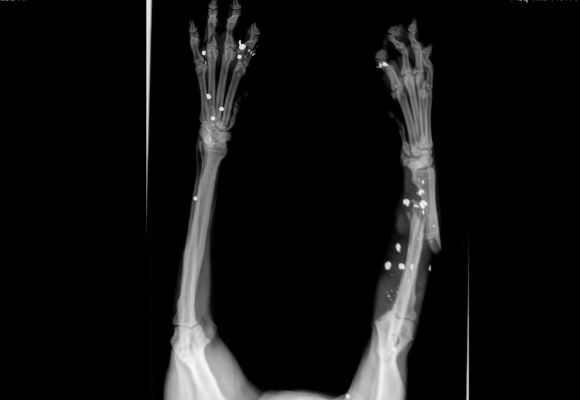

When Celia arrived at the Kentucky Humane Society, we noticed she wasn’t putting any weight on her front right leg. Worried, our veterinary team immediately took her in for x-rays. What we saw broke our hearts. We discovered that not only was Celia’s leg severely broken but it was also littered with shrapnel. This leads us to believe that this sweet girl was the victim of a gunshot, which ultimately caused her leg to break.

The bullets did irreparable damage to Celia’s leg, and our vet team decided that amputation was the only way to guarantee a full recovery. We performed the surgery yesterday and while Celia is recovering well, her healing journey is not yet over. While performing routine blood tests prior to surgery, we learned that Celia is heartworm positive. So, we immediately started treatment and for now, have her under close observation. We hope this sweet pup will be back on her feet once she is fully healed from heartworms and surgery. Please support lifesaving care for animals like Celia by donating in her honor using the button below, or online at kyhumane.org/donate. Together, we can provide every animal who comes through our doors with the tender loving care they deserve. Thank you!